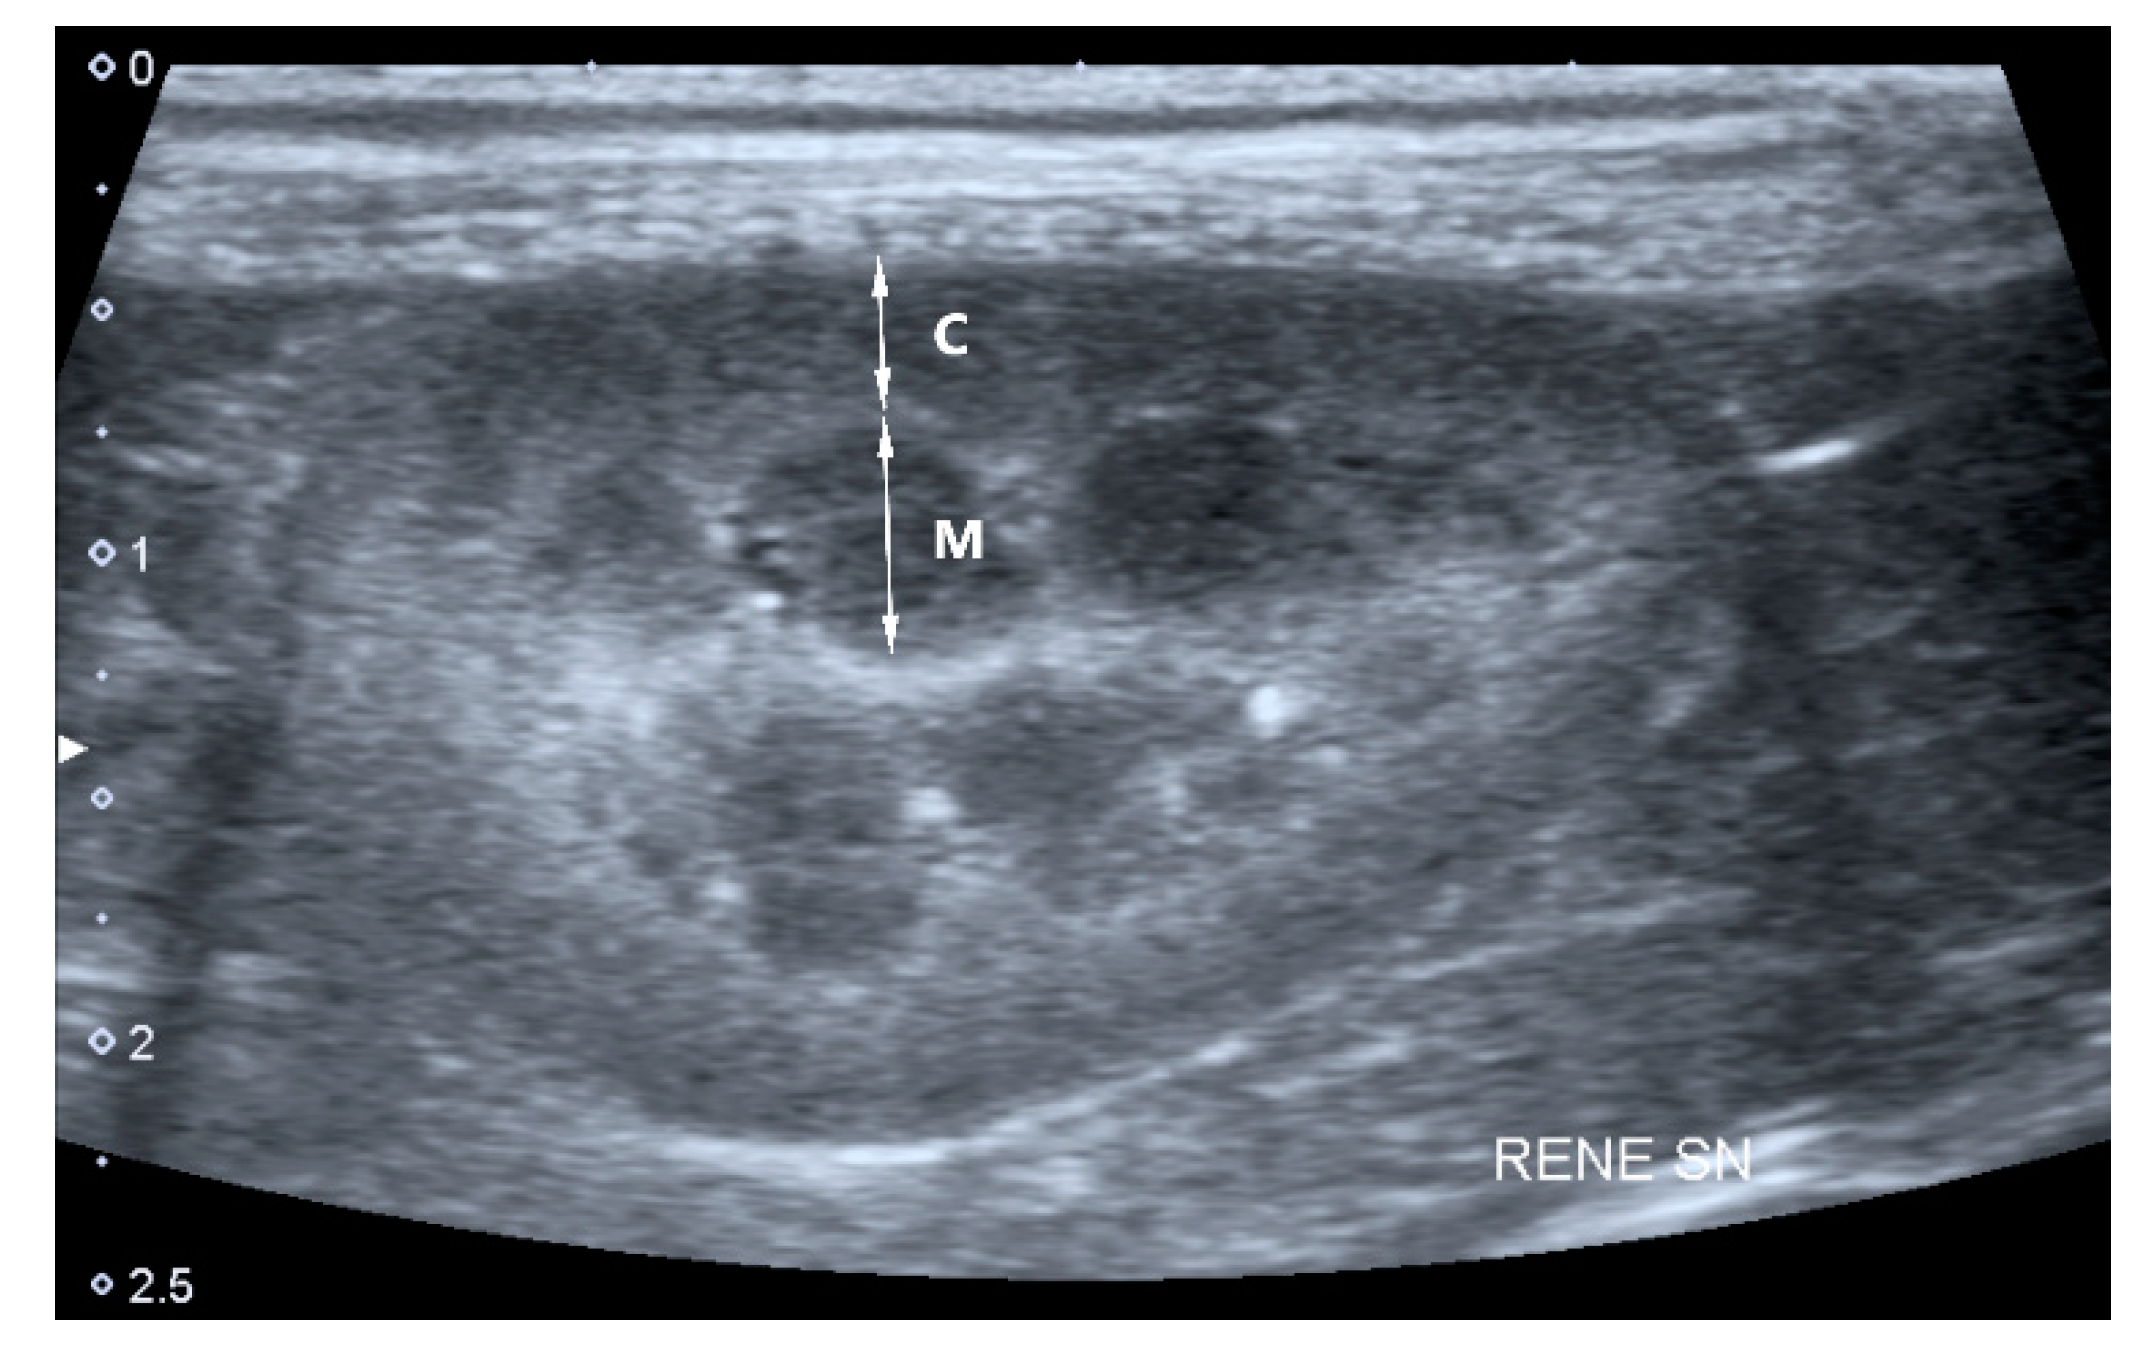

- Cortical and medullary ratio (C/M ratio): Normal (C/M ratio > 1:1) or abnormal (C/M ratio < 1:1). Cortical thickness was measured in the sagittal plane over a medullary pyramid, perpendicular to the capsule. Medullary thickness was measured from the renal hilum to the outer margin of the cortico-medullary junction (Figure 1).